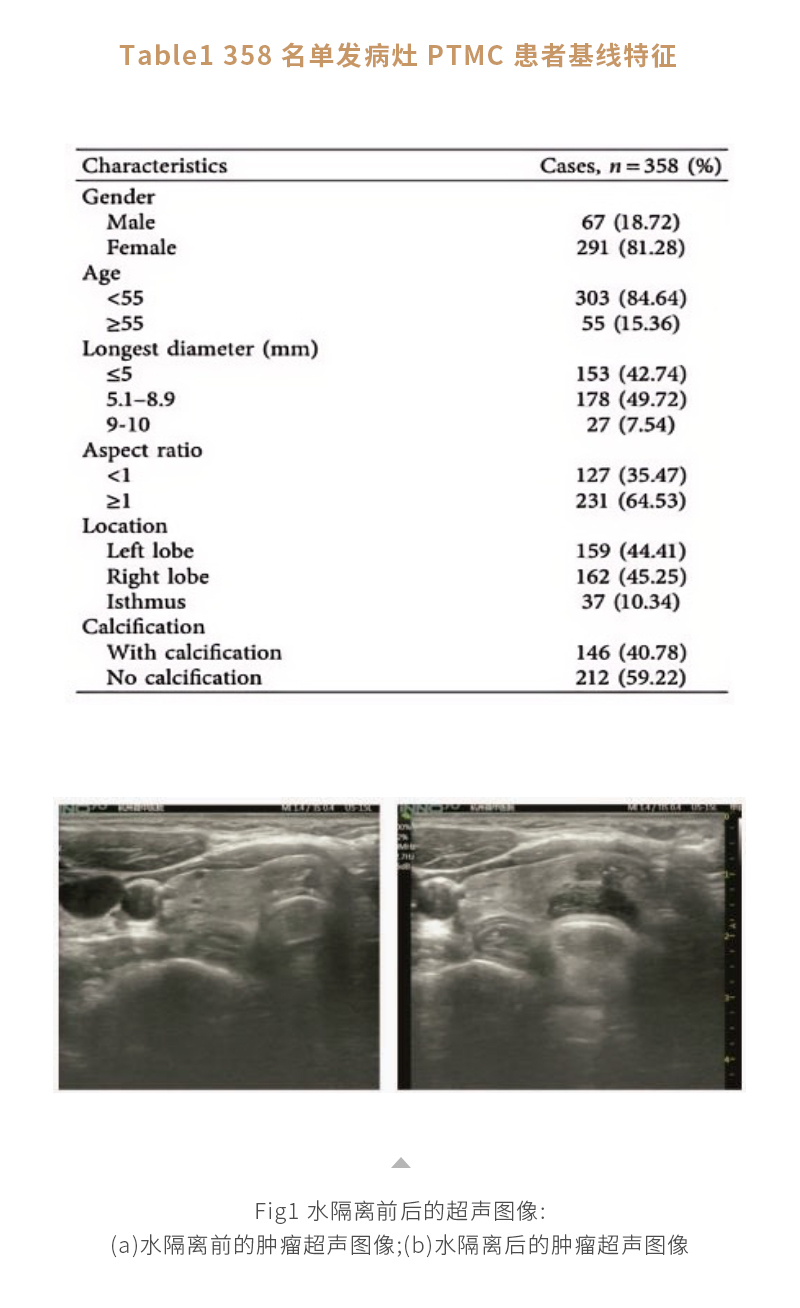

甲狀腺癌熱消融——【海杰亞科研資訊】第278期

發(fā)布時間:2024-08-16 | 作者:海杰亞 | 瀏覽次數(shù):1436